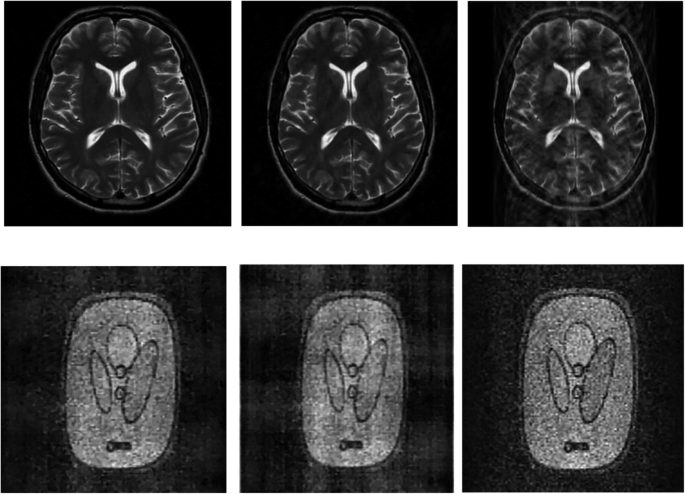

In this section, we present the results of one of the several experiments that we did demonstrating the visual quality of the reconstructed images using AS-DLMRI, DLMRI and LDP. For the results shown in Fig. 4 below, we used a sampling mask in k-space with 10 fold undersampling, and the number of iterations was fixed to ten. It was noted that the visual quality for the images reconstructed by AS-DLMRI and DLMRI were almost identical, and therefore no significance visual difference between the images reconstructed by both algorithms. However, we noted a significance difference in visual quality of AS-DLMRI and LDP. We did other experiments with different undersampling masks and altering the number of iterations for dictionary learning, and we observed that AS-DLMRI and DLMRI produced almost identical visual quality results with a significance difference in visual quality when compared to LDP.

Experiment on reconstruction visual quality. (Top row) (left)- reconstruction of an MRI image using our proposed algorithm AS-DLMRI, (middle)-reconstruction using DLMRI and (right)-reconstruction using LDP. (Bottom row) (left)- Reconstruction of a phantom image using AS DLMRI, (middle)-reconstruction using DLMRI and (right)-reconstruction using LDP